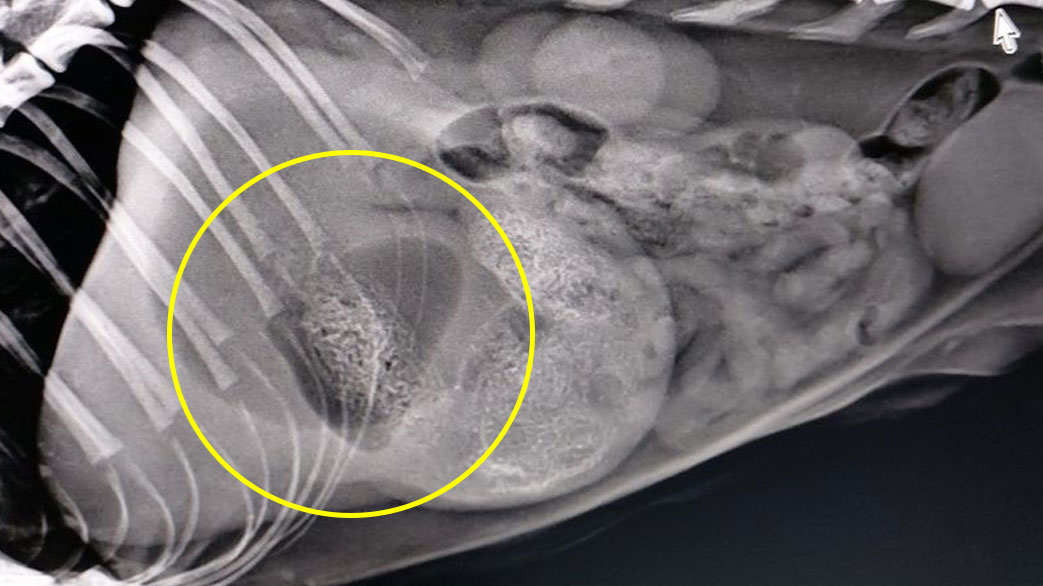

หมอจับ X-ray พบสิ่งแปลกปลอมอุดตันในกระเพาะอาหาร จนกระเพาะอาหารขยายขนาด แมวมีภาวะท้องกาง และผอมมาเลยค่ะ (1.8 kg)

วันนี้เลยผ่ากระเพาะ เจอต้นเหตุคือ มุ้งลวดจำนวนมากอัดในกระเพาะอาหาร นำออกมาให้หมดเรียบร้อยค่ะ